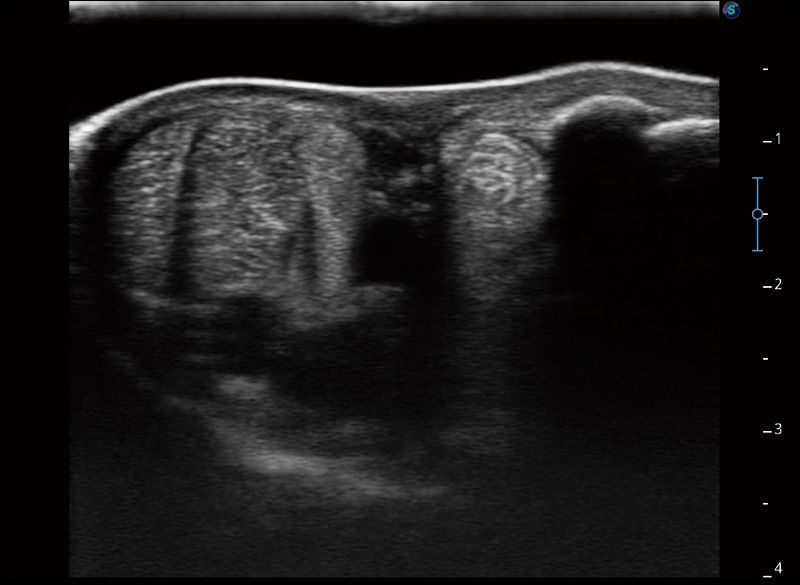

穿刺针增强

高清显示穿刺进针情况